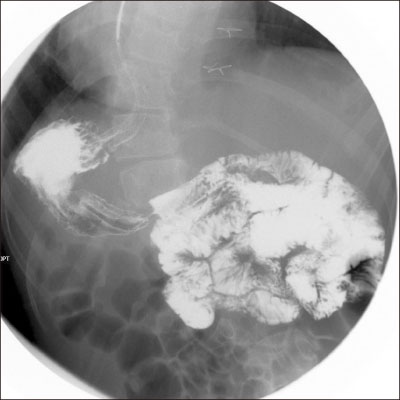

At the time of the current visit, the laboratory values were normal, except for the presence of leukocytosis (13,720/µL) and a C-reactive protein elevation to 1.85 mg/dL. Initial vital signs were stable at the time of the visit to the emergency department. On X-ray imaging, diffuse gaseous distension of colon was seen (

Fig. 2), and right-sided stomach gas was also seen, which was identified as SI at the previous visit to Seoul National University Hospital which was mentioned above.

Fig. 2Diffuse gaseous distension of colon on abdominal X-ray.